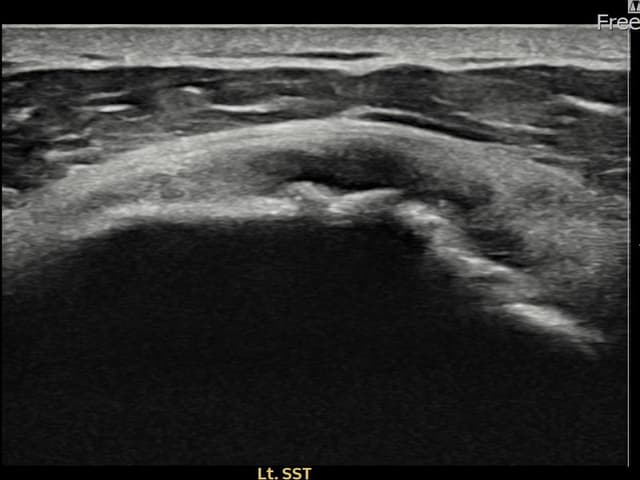

[촬영시기:22.10.06~22.11.14]

[어깨인대 축소봉합술] 좌측 어깨 극상근건 광범위 파열로 수개월간 일상생활이 어렵던 중 내원하셨습니다.